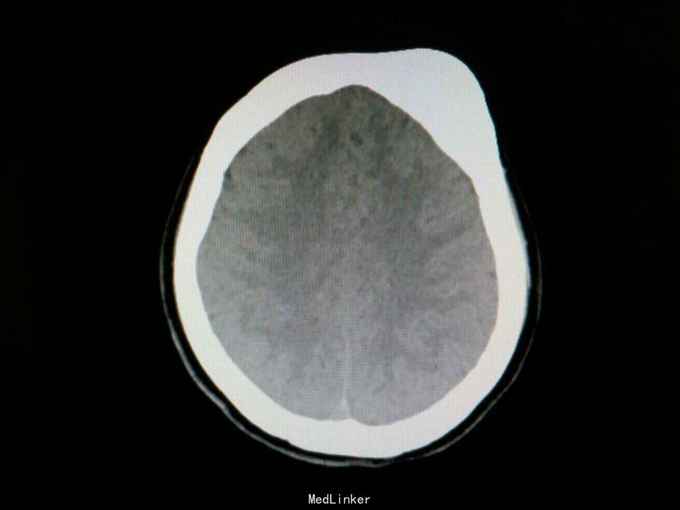

查体:生命体征平稳。左前额部见一大小约4×5cm大小肿物,质硬,压之无波动,无压痛,头面部无水肿,Horner征阴性,上腔静脉压迫综合征阴性,Pancoast征阴性,头颅无损伤。神经系统专科检查未见明显异常。 辅助检查:头颅CT检查提示双侧大脑及小脑半球对称,脑实质内未见异常密度影。脑室未见扩张。脑池、脑沟、脑裂未见增宽。中线结构居中。左侧额骨外板可见局限性骨性突起,大小约22mm×55mm(序列:4 ,层数:100),边缘光滑,内见斑片状骨密度影,密度不均。左侧额骨病变,考虑良性病变,骨纤维结构不良或骨化性纤维瘤。